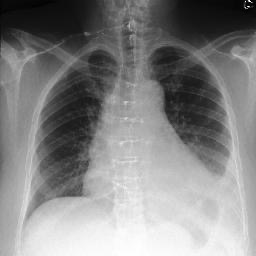

To address these issues, we propose a novel Adaptive patch-word Matching (AdaMatch) model to correlate chest X-ray (CXR) image regions with words in medical reports and apply it to CXR-report generation to provide explainability for the generation process. AdaMatch exploits the fine-grained relation between adaptive patches and words to provide explanations of specific image regions with corresponding words. To capture the abnormal regions of varying sizes and positions, we introduce the Adaptive Patch extraction (AdaPatch) module to acquire the adaptive patches for these regions adaptively. In order to provide explicit explainability for CXR-report generation task, we propose an AdaMatch-based bidirectional large language model for Cyclic CXR-report generation (AdaMatch-Cyclic). It employs the AdaMatch to obtain the keywords for CXR images and `keypatches' for medical reports as hints to guide CXR-report generation. Extensive experiments on two publicly available CXR datasets prove the effectiveness of our method and its superior performance to existing methods.